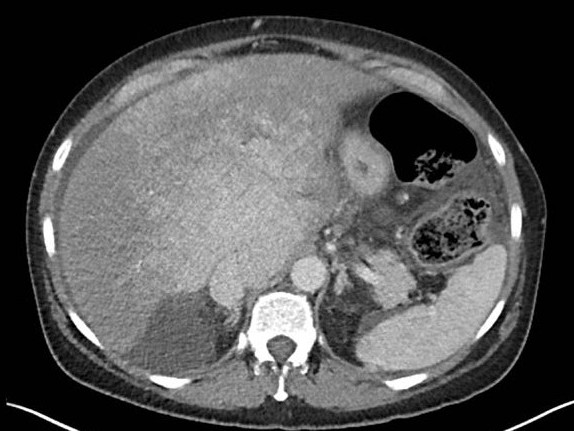

• Complex Intrahepatic Vascular Shunts in Hereditary Hemorrhagic Telangiectasia: From Portal Hypertension to High-Output Cardiac Failure

Filipe Nery, Diana Valadares, Manuel Teixeira Gomes

36-40

DOI: https://doi.org/10.60591/crspmi.557